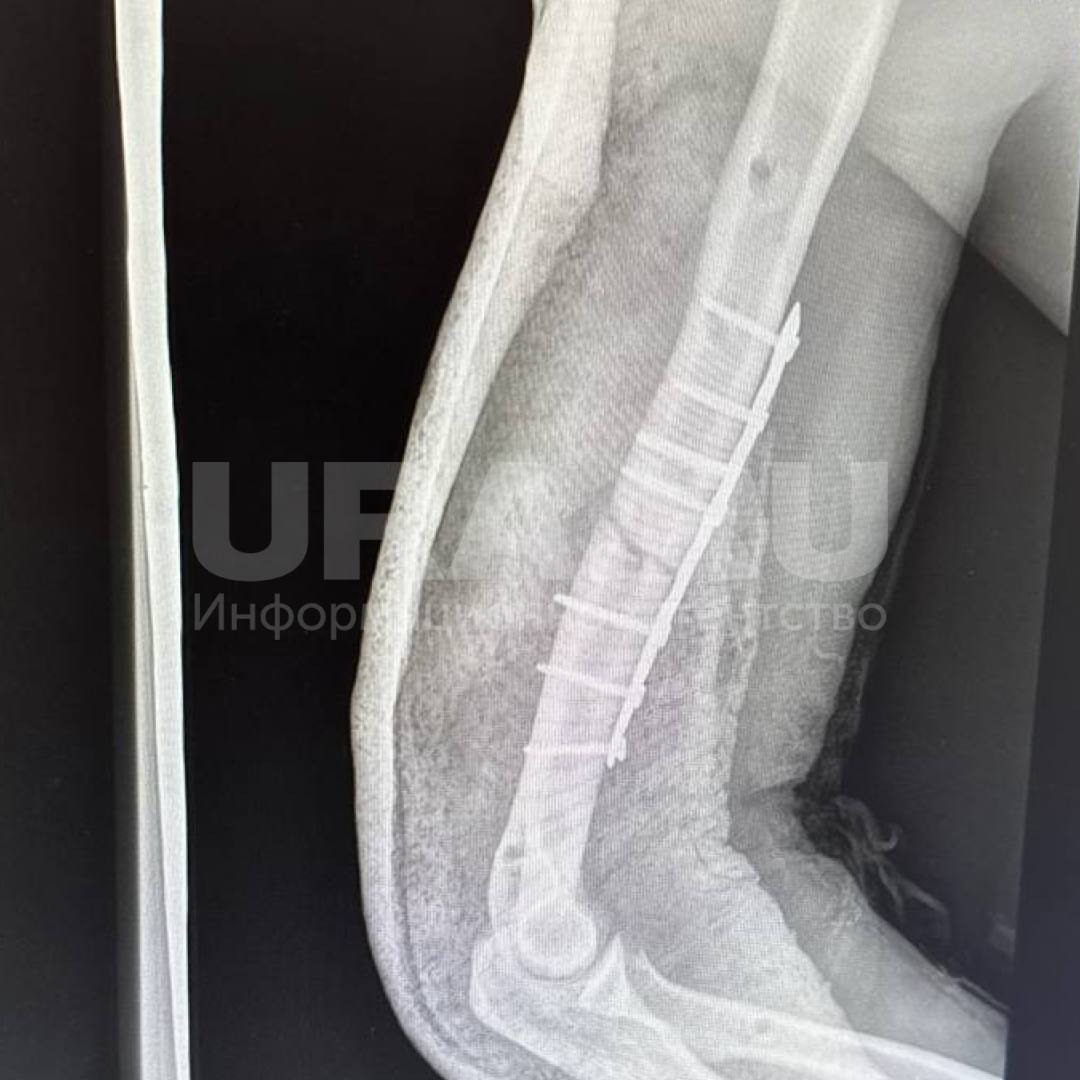

Упал с 32-го этажа и остался жив. Хирурги два месяца заново собирали скелет рабочего, сорвавшегося на стройке. По информации URA.RU, монтажника спасло защитное сооружение, на него он рухнул пролетев 20 этажей. Получил 10 переломов: носа, обоих плечей, ребер, костей таза и ног. Одно легкое оказалось разорванным. К жизни пациента вернули в НОКБ им. Семашко.